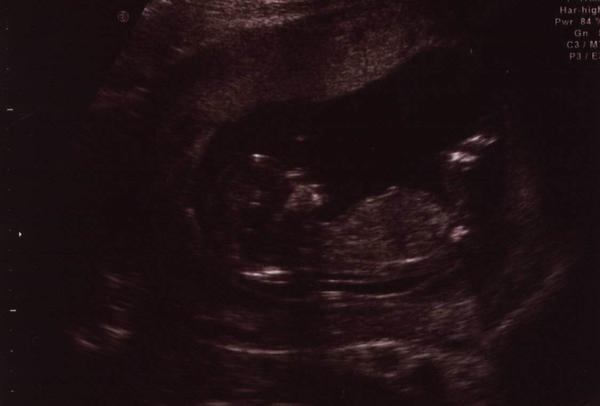

@littlemousecz moc hezká fotečka, už předběžně víte co by to mohlo být?? Nebo je to tajemství?? 😉

@petrufa86 díky. ještě to nevíme ani předběžně a nejsem ani rozhodnutá, jestli si to necháme říct. Já bych ani nemusela ale Honza by to chtěl vědět.

@littlemousecz aha, já myslela že už to třeba víte. Ségře to dr při prvotrimestr. screeningu řekl na 80% co čekají.

@martina_81 no to je ultrazvuk, na kterým zkoumají šíjový projasnění, přítomnost nosní kůstky, přítomnost orgánů (srdce, mozek, žaludek, močový měchýř, bránice,...), pak ještě ti vezmou krev kvůli hladině nějakých hormonů a pak podle toho určí pravděpodobnost, že bude mít miminko nějaký postižení. Nám třeba vyšla pravděpodobnost na Downa 1:20000, takže se snad nemusíme ničeho bát.Za riziko se považuje pravděpodobnost 1:300 a nižší. Pak se dělá ještě screening ve 20 tt, tam se zkoumají vrozený vývojový vady (srdce, rozštěpy)